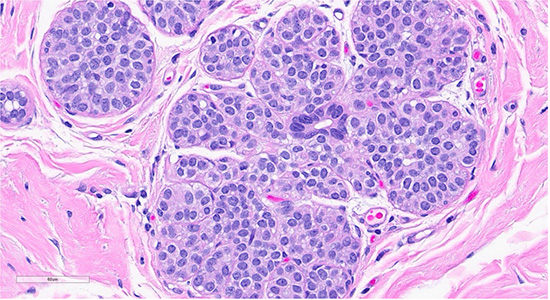

Figure 3: Microscopic slides of atypical ductal hyperplasia. The H&E section shows expanded ducts filled with monomorphic epithelial cells arranged in a mixed solid and cribriform pattern; the focus measures 2.5 mm

Histological examination revealed lobules containing cells arranged in a cribriform pattern with eosinophilic to basophilic, round to oval, collagen-rich spherules (in this case mucinous spherules - may be called mucinous spherperolosis instead). Adjacent regions demonstrated a monomorphic proliferation of mildly atypical cells with round nuclei, indistinct nucleoli, and dyshesive features, along with intracytoplasmic lumina. Other foci were composed of ducts with monomorphic cells displaying ovoid to rounded nuclei in a solid and cribriform pattern, each focus measuring less than 2 mm. A focal area displayed ducts filled with polymorphous cells with peripheral elongated clefts. Additional ducts exhibited an architecturally “flat” pattern without cytologic atypia. The epithelial lining cells were predominantly columnar, with elongated nuclei oriented perpendicular to the basement membrane.